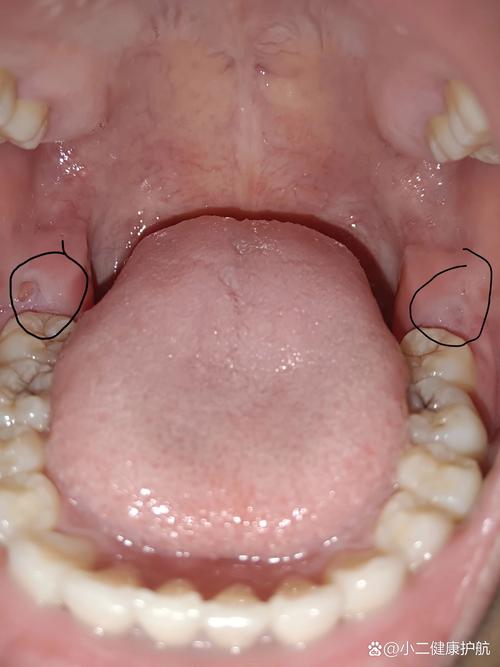

智齿冠周炎

这是由细菌感染引起的更严重的炎症,其表现更像是“脓肿”或“炎性包块”。

- 红肿:主要发生在智齿后方的牙龈组织,肿胀范围可能很大,甚至延伸到脸颊外部,导致脸颊鼓起。

- 化脓:在肿胀的牙龈顶端,可能会看到黄色的脓点或脓液渗出,这是典型的感染迹象。

- 疼痛:呈持续性、搏动性剧痛,并可能放射到耳部、头部、下颌,导致张口困难、吞咽疼痛。

- 全身症状:严重时可能伴有发烧、乏力、头痛等全身不适。

(图片说明:下颌智齿后方牙龈红肿、隆起,并可见白色脓点,这是典型的智齿冠周炎表现。)